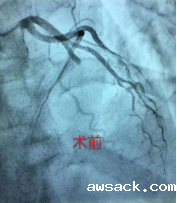

冠状动脉介入治疗:经桡动脉路径,疏通狭窄甚至闭塞的冠状动脉管腔,从而改善心肌的血流灌注。